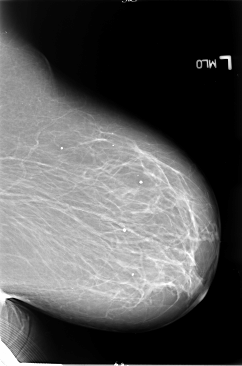

ics_version 1.0 filename B-3065-1 DATE_OF_STUDY 14 3 1994 PATIENT_AGE 69 FILM FILM_TYPE REGULAR DENSITY 2 DATE_DIGITIZED 15 9 1997 DIGITIZER LUMISYS LASER SEQUENCE LEFT_CC LINES 5880 PIXELS_PER_LINE 3664 BITS_PER_PIXEL 12 RESOLUTION 50 NON_OVERLAY LEFT_MLO LINES 5856 PIXELS_PER_LINE 3864 BITS_PER_PIXEL 12 RESOLUTION 50 NON_OVERLAY RIGHT_CC LINES 5704 PIXELS_PER_LINE 3504 BITS_PER_PIXEL 12 RESOLUTION 50 OVERLAY RIGHT_MLO LINES 5736 PIXELS_PER_LINE 3576 BITS_PER_PIXEL 12 RESOLUTION 50 OVERLAY |